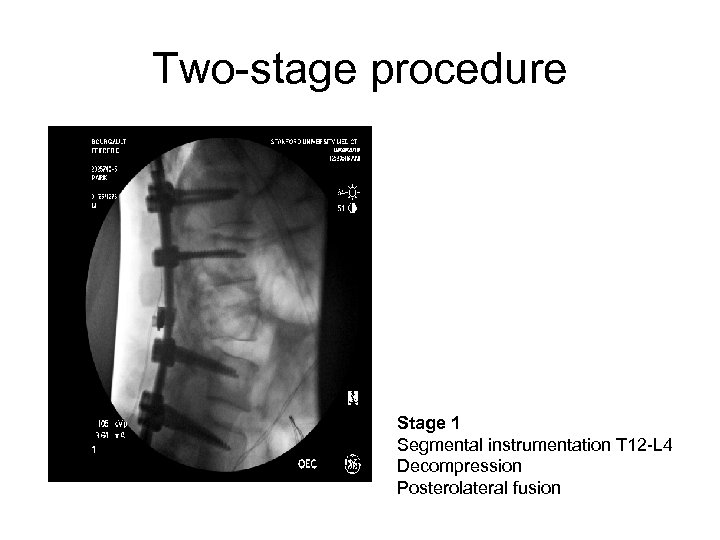

Two-stage procedure Stage 1 Segmental instrumentation T 12 -L 4 Decompression Posterolateral fusion